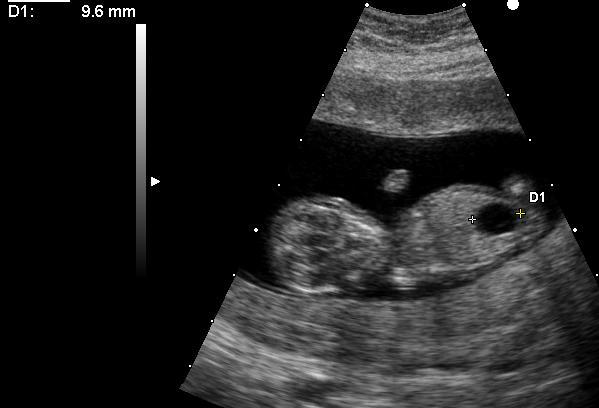

Méga vessie chez un embryon porteur d'une trisomie 21.Megacystis in embryo with Down'syndrome.

Author X.Compagnion